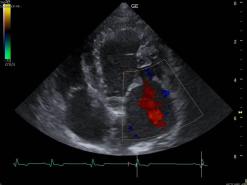

In der Ultraschalluntersuchung (Echokardiografie) werden die einzelnen Strukturen des Herzens und auch ihre Funktionen beurteilbar. Die Herzklappen, der Herzmuskel und der Blutfluss im Herzen wird dabei visualisiert.

Mit dem Ultraschall werden der Herzmuskel und seine Anhänge dargestellt. Die verdickten Klappenteile, das Ausmass des Pendelblutes, der vergrösserte Vorhof und Ventrikel sowie die Druckdifferenzen sind mess- und darstellbar. Nach dieser systematischen Erfassung und Beschreibung beurteilt die Tierärztin den Schweregrad der Erkrankung und definiert Therapie-Optionen.

Ausmass des Pendelblutes in den linken Vorhof in Farben.

Farb-Doppler Darstellungen